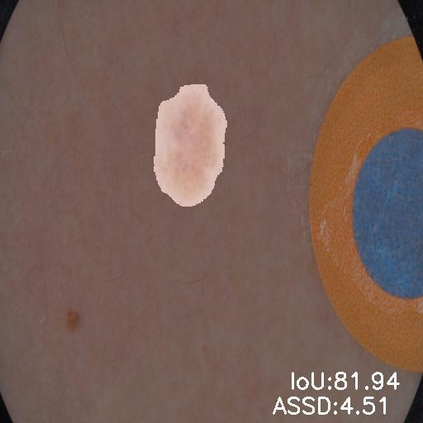

Skin lesion segmentation from dermoscopy images is of great significance in the quantitative analysis of skin cancers, which is yet challenging even for dermatologists due to the inherent issues, i.e., considerable size, shape and color variation, and ambiguous boundaries. Recent vision transformers have shown promising performance in handling the variation through global context modeling. Still, they have not thoroughly solved the problem of ambiguous boundaries as they ignore the complementary usage of the boundary knowledge and global contexts. In this paper, we propose a novel cross-scale boundary-aware transformer, \textbf{XBound-Former}, to simultaneously address the variation and boundary problems of skin lesion segmentation. XBound-Former is a purely attention-based network and catches boundary knowledge via three specially designed learners. We evaluate the model on two skin lesion datasets, ISIC-2016\&PH$^2$ and ISIC-2018, where our model consistently outperforms other convolution- and transformer-based models, especially on the boundary-wise metrics. We extensively verify the generalization ability of polyp lesion segmentation that has similar characteristics, and our model can also yield significant improvement compared to the latest models.